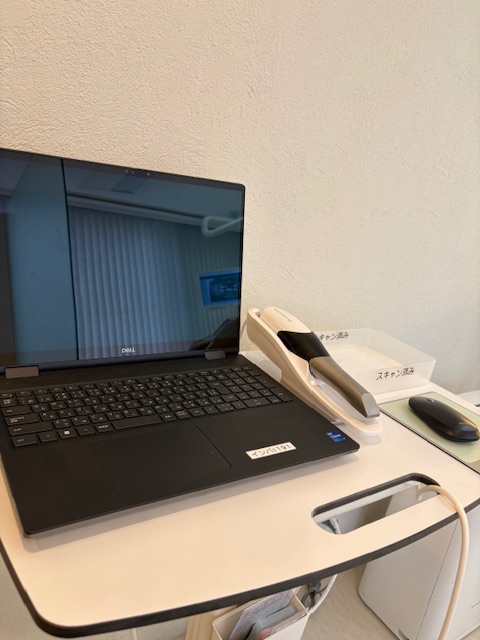

天野歯科では最新の口腔内スキャナーによりデジタルインプレッションにてジルコニアを作製しますので従来より一層精密正確に仕上げられる様になっております。